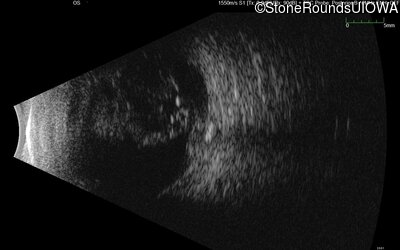

B-Scan Ultrasonography - Right - 20/300 sc

Exemplar